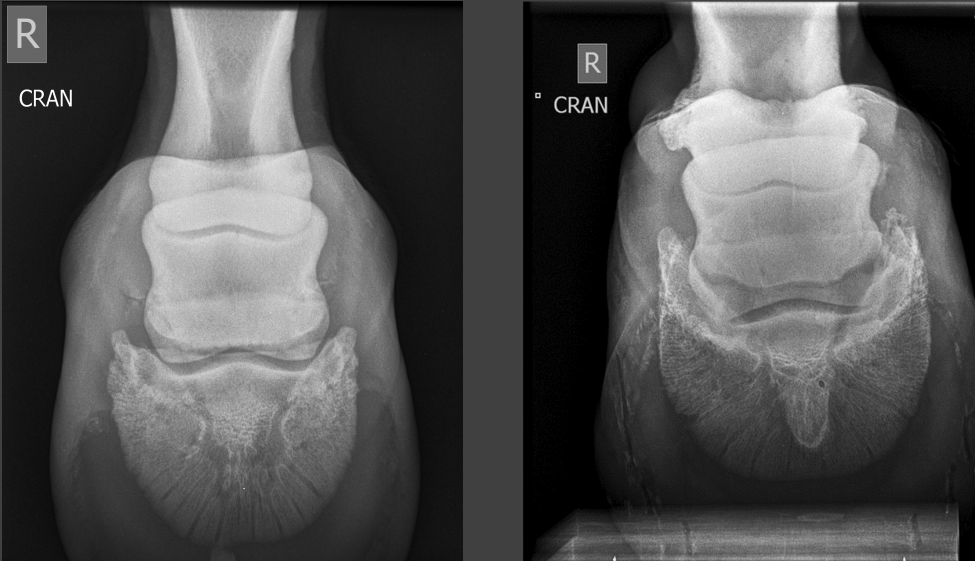

A

splint bone fractures